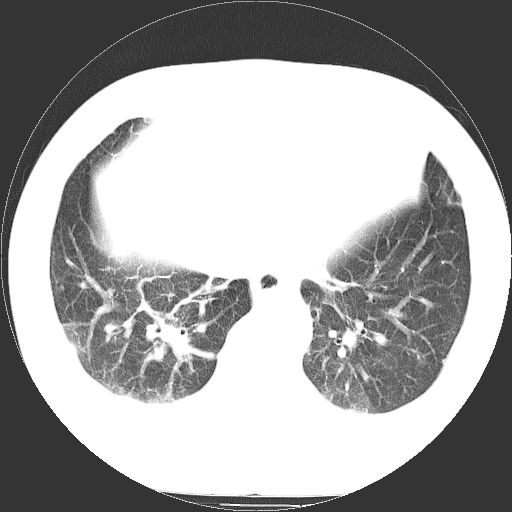

标题: CT21804:男,65岁,咳嗽、咳痰、发热5天。 [打印本页]

男,65岁,咳嗽、咳痰、发热5天。

慢支 肺间质纤维化合并感染!

支气管扩张合并感染,胸膜肥厚

考虑慢支并感染,肺间质纤维化。

两肺间质性炎症并感染

两肺间质纤维化,支扩合并感染,双侧胸腔积液

感染,肺间质纤维化。

慢支 肺间质纤维化合并感染

支持慢性支气管、肺间质纤维化合并感染。

慢性支气管炎并感染,支扩,双侧少量胸腔积液.